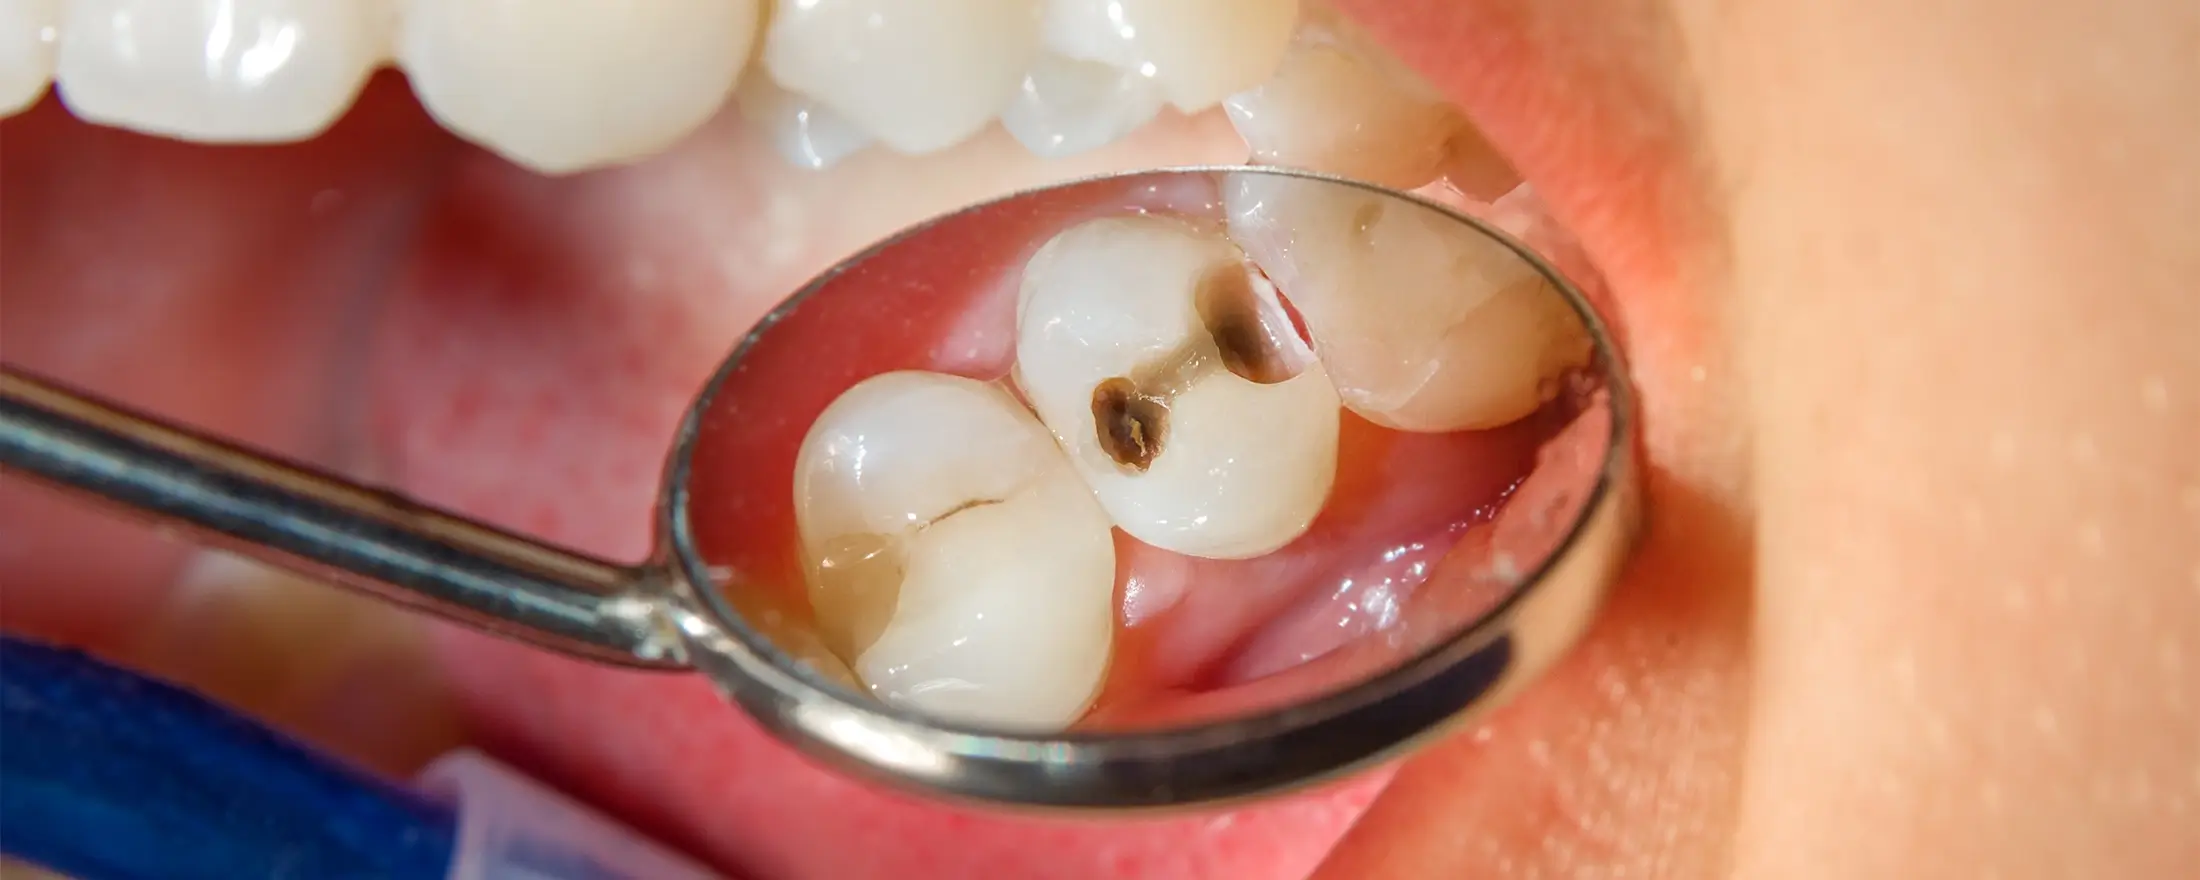

虫歯を削った歯にレジン(複合樹脂)を直接詰める治療法です。保険診療では、15〜30分の限られた時間内で、保険制度で定められた範囲内の基本的な処置のみを行うことになります。

| 再発の リスク | 隙間から再発しやすい |

- 虫歯の範囲によっては適用外